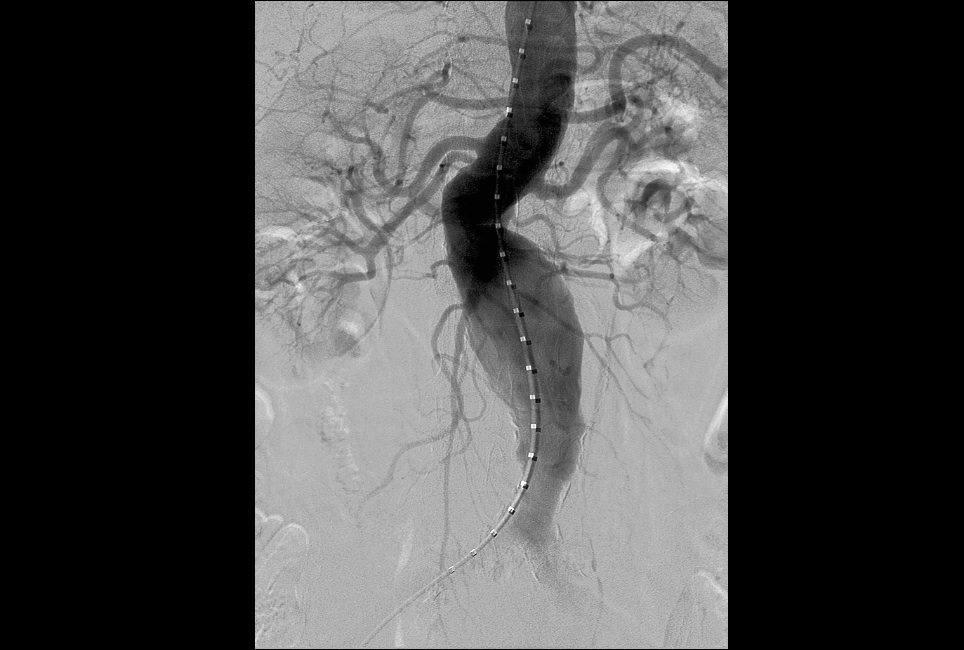

2.外周血管介入手术治疗:腹主动脉血管病症,肝脏肿瘤治疗,肝脏,肺部肿瘤活检,椎体成形术,泌尿系统血管病变等微创介入手术。

左下肺动脉造影 右下肺动脉造影 图左:腹主动脉瘤造影 图右:腹主动脉瘤支架植入造影